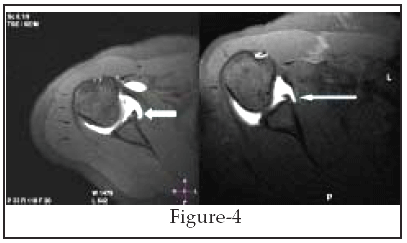

At arthroscopy, 21 anteroinferior labroligamentous lesions were diagnosed, including 15 Bankart lesions Fig (1,2),3 ALPSA lesions(Fig-3), 2 Perthes lesions (fig-4), and 1 GLAD lesion (Fig-5). Seven labral lesions were nonclassifiable at arthroscopy, all of which occurred after a history of chronic instability. When compared with arthroscopic findings, Shoulder MR Arthrography had two false-negative results (sensitivity, 92.8%) and no false-positive results. The sensitivity of Shoulder MR Arthrography in detecting anteroinferior labroligamentous lesions was 92.8% (26/28), and specificity was (100%). The overall accuracy of Shoulder MR Arthrography in detecting labroligamentous lesions in our study was 90.5% (19/21).

Fig-4: Perthes Lesion. An axial T1 weighted spin echo MR arthrogram with fat saturation shows an undisplaced avulsed anteroinferior labrum with medial stripping of an intact periosteum consistent with a Perthes lesion (arrow). This lesion is better visualized when stress is applied such as during abduction and external rotation ABER position.